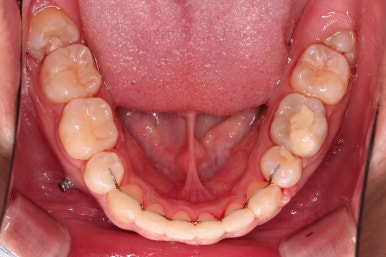

장치를 처음 부착한 모습입니다.

이번 환자분이 선택하신 장치는 데이몬 클리어라고 하는 자가결찰 세라믹 장치인데요.

흔히들 아시는 클리피씨 장치 등등에 비해 현존하는 브라켓 중에 가장 심미적인 장치입니다.

이 때 필요한 것이 미니스크류 입니다.

예전과는 다르게 미니스크류를 이용해서 좀 더 정교하고 고난이도의 치료가 가능해지게 된거죠.